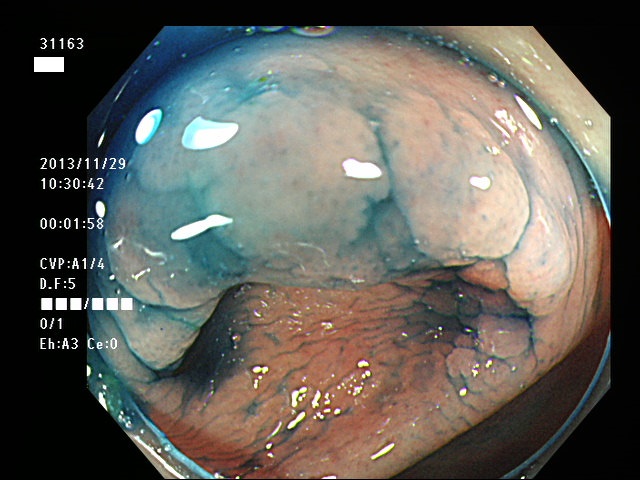

虫垂開口部の過形成ポリープ(SSAP)の例